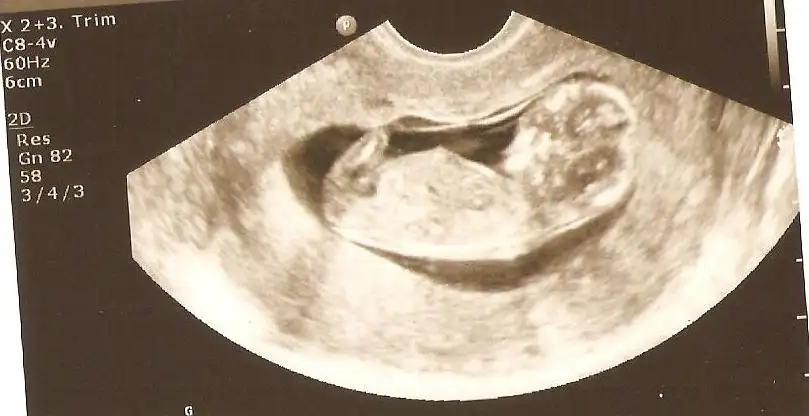

İlk iki resim 12+3 , diğer ikisi 12+6

Malesef resimler biraz önden. İlk resimlerde tam çekip, ikincilerinde yaklaştırıp screenshot yapıp ekledim.

Teşekkürler :)